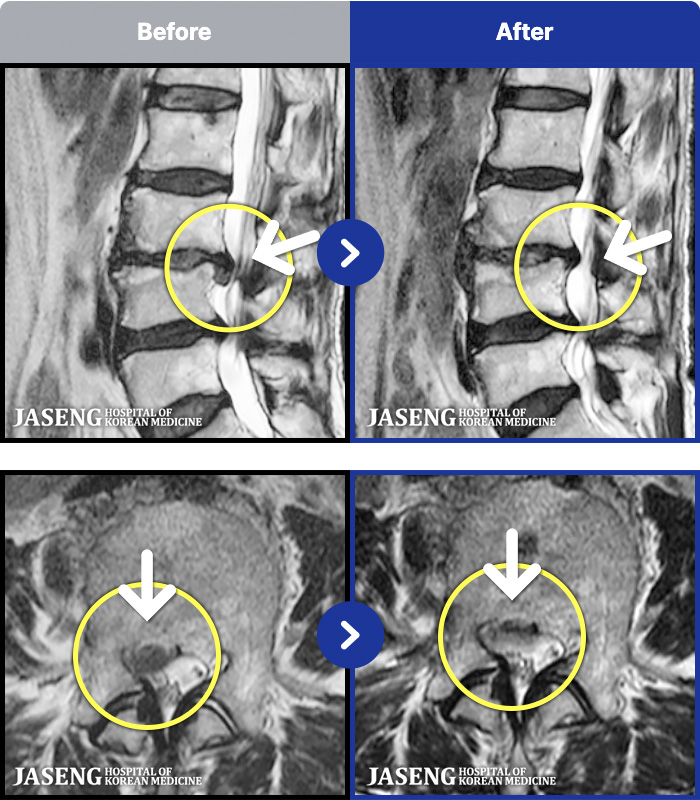

MRI ġ

1,301 MRI ũ ʸ Ȯϼ.